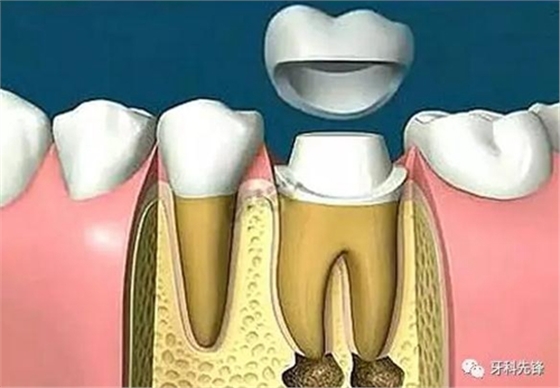

由于這3個(gè)方面的原因,整個(gè)牙齒的支持力量明顯減弱,可能在某些特定條件下不足以支持咀嚼壓力而容易發(fā)生牙冠劈裂,所以要及時(shí)做個(gè)牙冠把牙齒保護(hù)起來。

當(dāng)牙齒做完根管治療,由于牙齒自身的結(jié)構(gòu)及治療的需要,牙冠中心一般都是空的,這時(shí),如果直接做牙套,其抗折斷力很差,一般都需要在牙根上打上樁釘,做出個(gè)結(jié)實(shí)的核,以對(duì)抗牙齒使用中的折斷力。

對(duì)于后牙來說,做完根管治療之后一定要做上牙冠,否則在承受咬合力量時(shí),牙齒容易出現(xiàn)斷裂。少數(shù)做完根管治療的后牙,若是要做單一的牙冠,只需將所剩牙質(zhì)修補(bǔ)足夠,則可不需做樁釘,但若做完根管治療的后牙是要作為假牙的基牙,則無論牙質(zhì)所剩多少,最后都能做好樁釘。